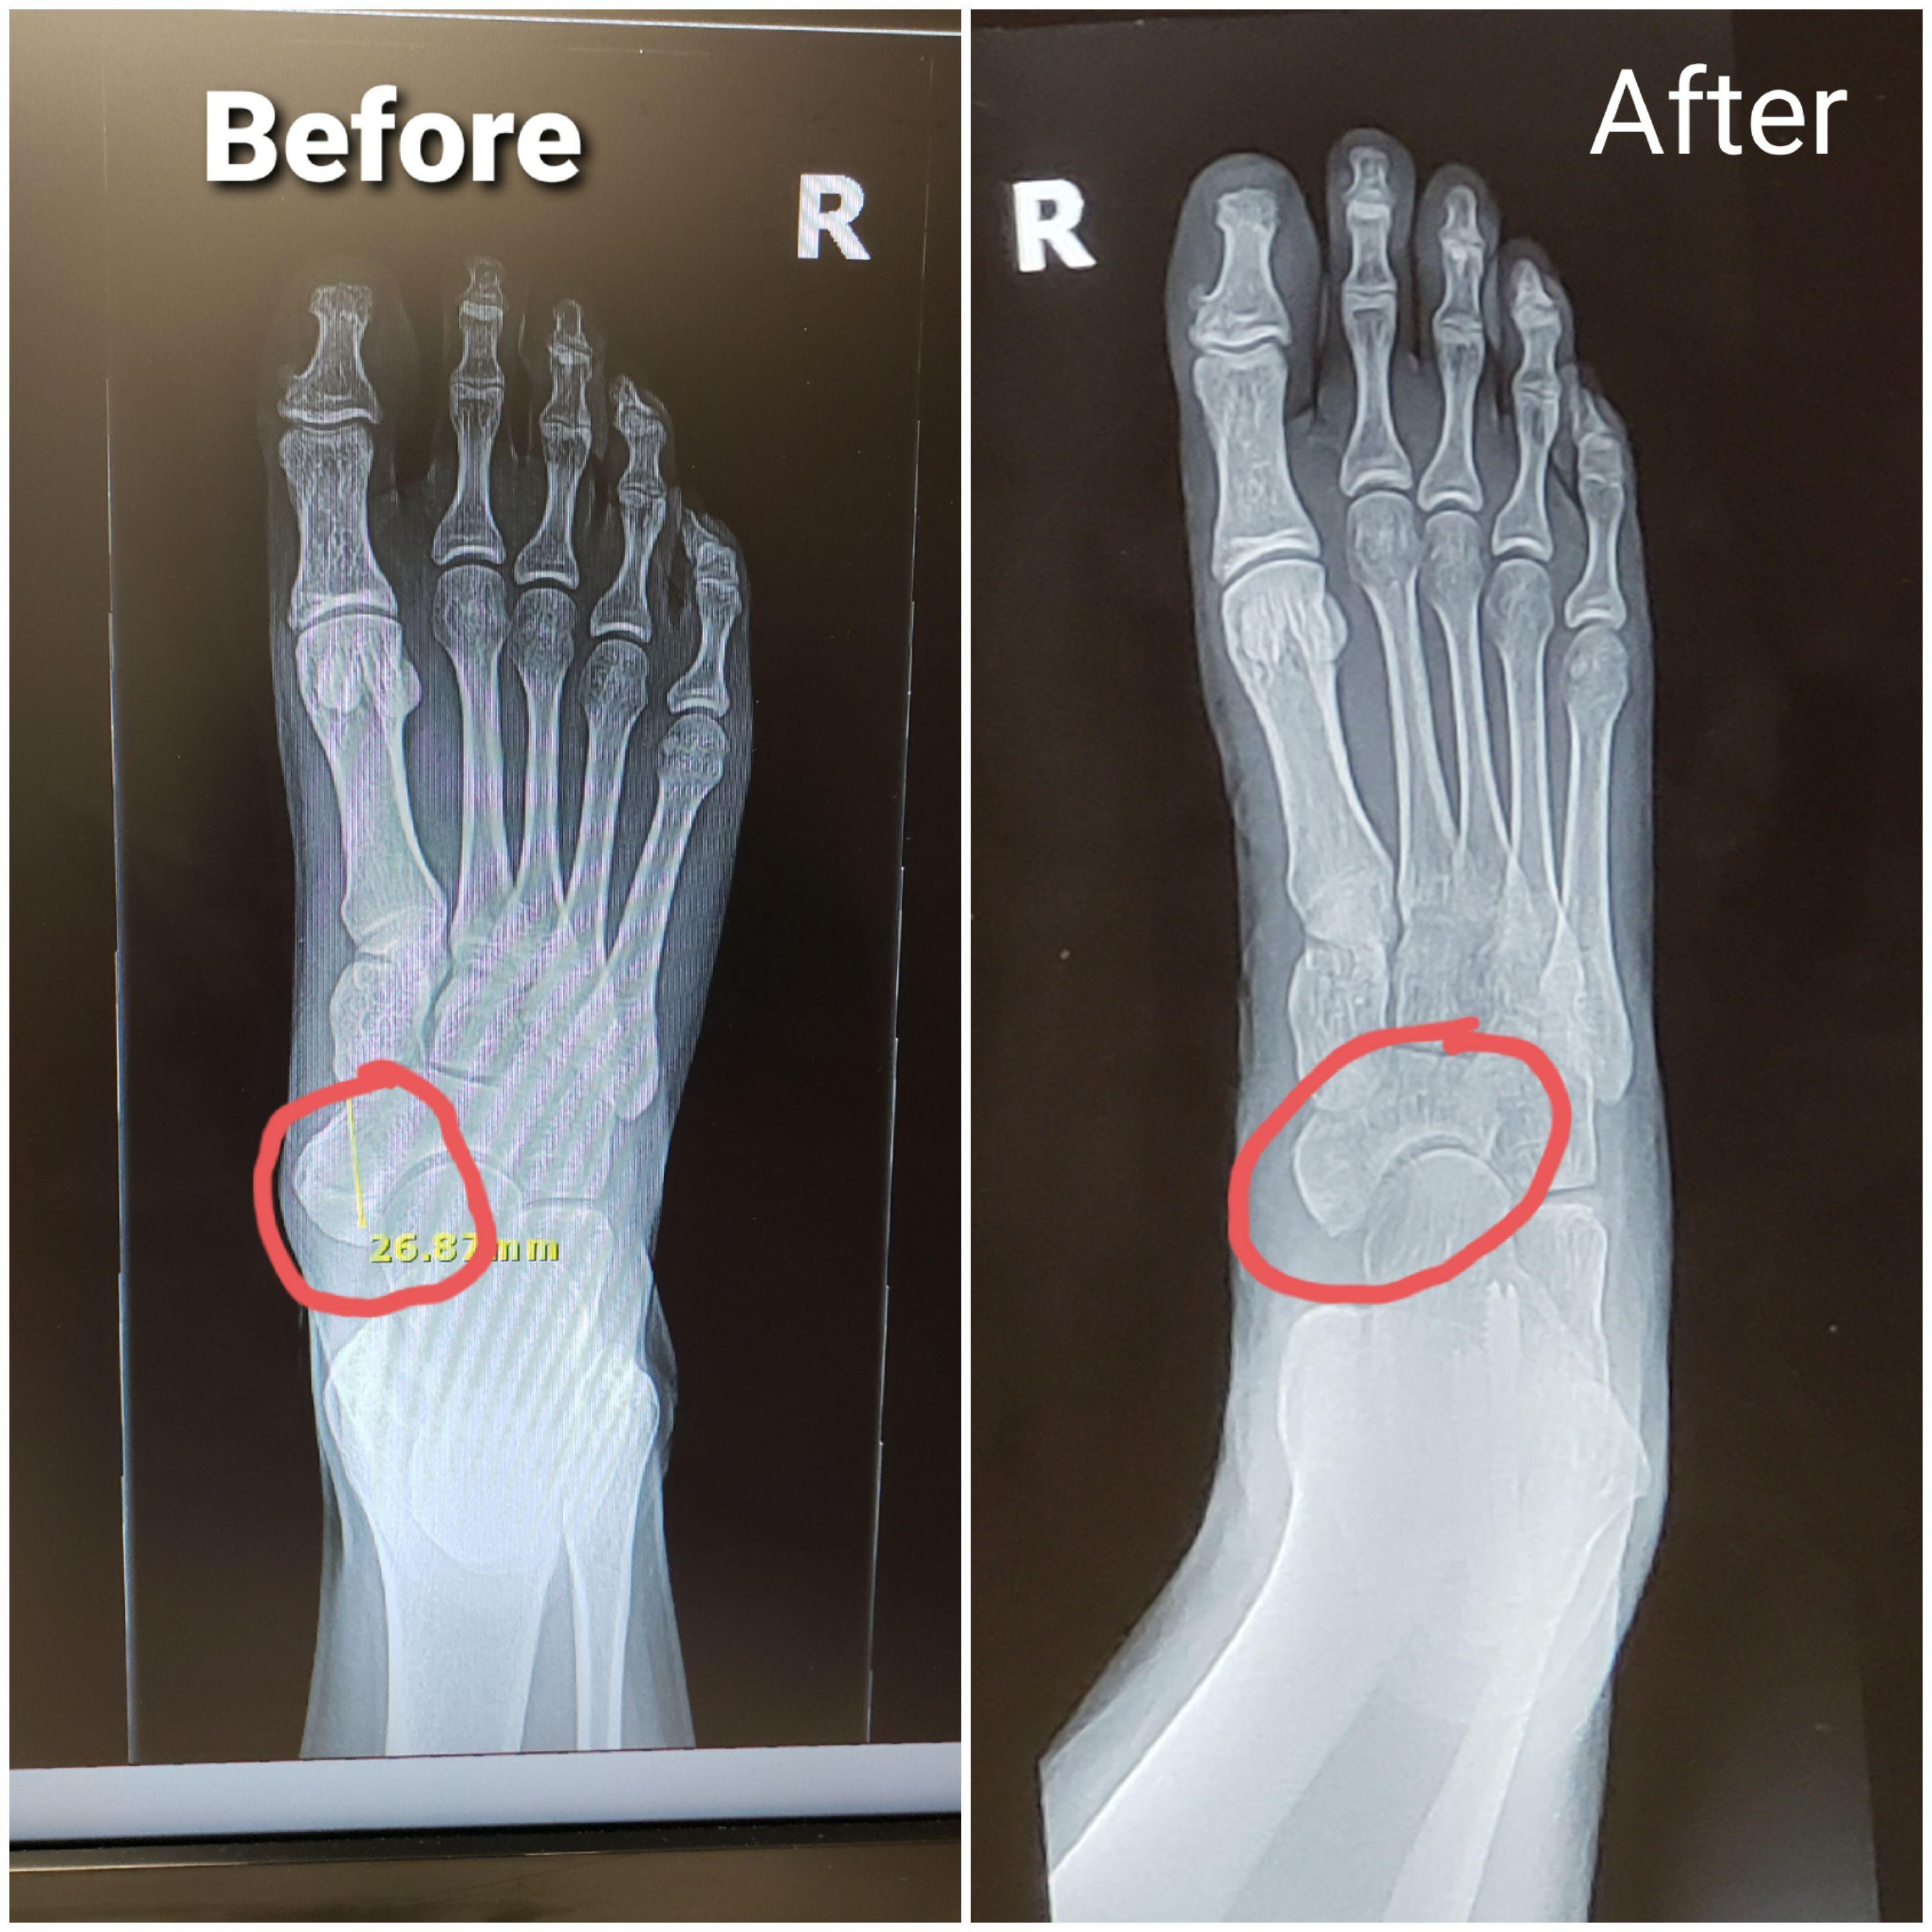

My Accessory Navicular in my RT foot before and after surgery. r Accessory Navicular Surgery Pain The risks of surgery are small and. Previous research on this topic has seen a low success rate in treating patients with symptomatic accessory navicular using conservative treatment. Insoles and stiff soled shoes such as walking boots or even custom shoes. Very rarely is a steroid injection warranted or recommended. Accessory navicular pain tends to be focused around the medial. Accessory Navicular Surgery Pain.